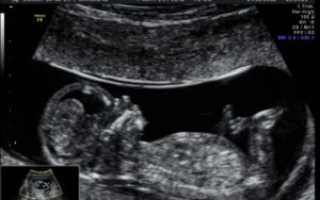

На больших сроках состояние плода и женщины исследуют с помощью абдоминального датчика через стенку брюшины. Такое обследование безопасно как для будущей матери, так и для плода.

Проведение третьего УЗИ выполняется трансабдоминально, т.е. через живот без вагинального датчика. Пациентку в специально оборудованном кабинете укладывают на кушетку на спину. Живот должен быть полностью освобожден от одежды.

На его область в небольшом количестве наносится специальный гель-проводник, по которому и выполняется движение датчика.

Врачом осуществляется перемещение датчика по всей поверхности стенок для оценки всех органов плода, оценки состояния матери и тех составляющих, которые отвечают за поддержку жизни будущего человека.

Сам способ проведения третьего УЗИ мало отличается от предыдущих осмотров. Женщина должна лечь на спину на кушетку, ноги при этом согнуты в коленях или лежат горизонтально. Доктор с помощью датчика проводит осмотр. Особенности УЗИ, третьего скрининга:

• Используется абдоминальный датчик. Определение всех интересующих параметров производится через живот.

• Применяется допплерография. Это метод, позволяющий оценить кровоток в сосудах пуповины, что важно для диагностики гипоксии плода.

Для выполнения последней плановой ультрасонографии используют абдоминальный датчик, будущая мамам должна занять на кушетке удобное положение и слушать комментарии врача-сонолога